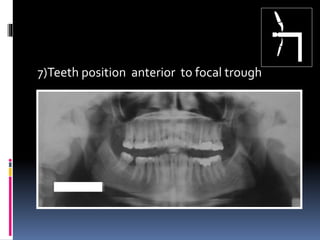

7)Teeth position anterior to focal trough